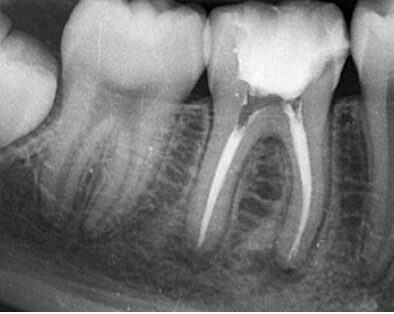

Endodontics

The treatment of dental canals, eliminating capillary and nerve pulp, allows the reconstruction of the pieces that are still viable for use when they have suffered problems of pain or infection due to caries or deep trauma.